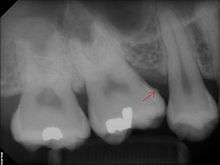

The processes of calculus formation from dental plaque are not well understood. Supragingival calculus formation is most abundant on the buccal (cheek) surfaces of the maxillary molars and on the lingual (tongue) surfaces of the mandibular incisors.[13] These areas experience high salivary flow because of their proximity to the parotid and sublingual salivary glands. Subgingival calculus forms below the gumline and is typically darkened in color by the presence of black-pigmented bacteria,[13] whose cells are coated in a layer of iron obtained from heme during gingival bleeding.[14] Dental calculus typically forms in incremental layers[15] that are easily visible using both electron microscopy and light microscopy.[7] These layers form during periodic calcification events of the dental plaque,[13] but the timing and triggers of these events are poorly understood. The formation of calculus varies widely among individuals and at different locations within the mouth. Many variables have been identified that influence the formation of dental calculus, including age, gender, ethnic background, diet, location in the oral cavity, oral hygiene, bacterial plaque composition, host genetics, access to professional dental care, physical disabilities, systemic diseases, tobacco use, and drugs and medications.[13]

Sub-gingival calculus (tartar) is composed almost entirely of two components: fossilized anaerobic bacteria whose biologic composition has been replaced by calcium phosphate salts, and calcium phosphate salts that have joined the fossilized bacteria in calculus formations. The initial attachment mechanism and the development of mature calculus formations are based on electrical charge. Unlike calcium phosphate, the primary component of teeth, calcium phosphate salts exist as electrically unstable ions. The following minerals are detectable in calculus by X-ray diffraction: brushite (CaHPO4·2H2O), octacalcium phosphate (Ca8H2(PO4)6.5H2O), magnesium-containing whitlockite (Ca9(MgFe)(PO4)6PO3OH), and carbonate-containing hydroxyapatite (approximately Ca5(PO4)3(OH) but containing some carbonate).[29]